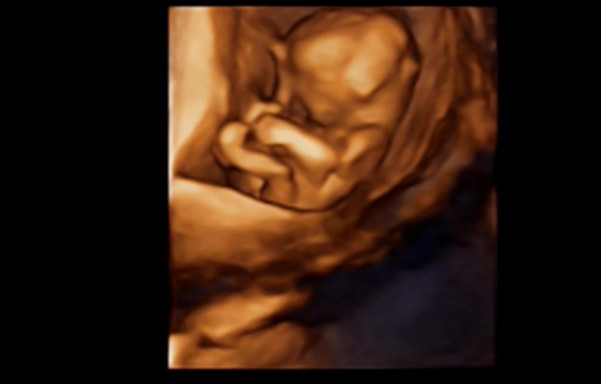

27岁的曹女士,已经怀孕六个月了。三天前,“孕味十足”的她,在丈夫的陪同下来到医院,准备进行提前预约好的四维彩超检查。但是万万没想到,检查结果让她的心情一下跌入低谷!通过影像显示,胎儿嘴唇中间竟然有一指宽的裂痕。经过医生再次仔细确认,腹中的胎儿确实患有唇腭裂,也就是“兔唇儿”。

唇腭裂患儿,是由于牙槽突间骨组织的缺失,造成上颌牙弓的完全性丧失,鼻基底部塌陷,牙槽突裂隙部恒尖牙萌出受阻。胎儿出生以后,需要通过牙槽突植骨术来完成唇部整形。手术具体怎么做,什么时候做,要做几次,这些都要根据孩子的具体病情。至于是否要生出来,这个就要由孕妇及家人自己决定。